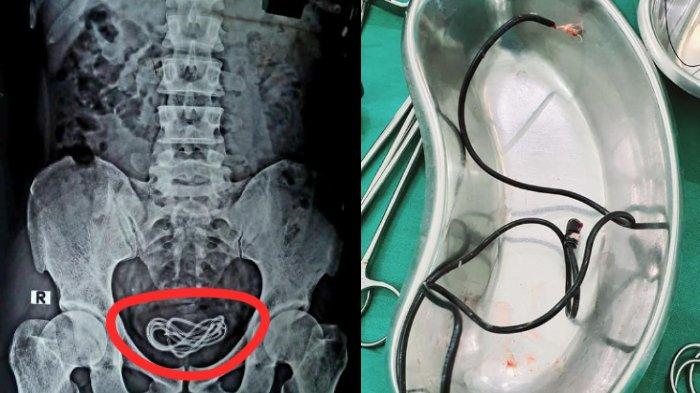

Tim dokter di India berhasil mengangkat kabel cahrger yang memiliki panjang hampir dua kaki (50 cm) dari kandung kemih pria berusia 30 tahun itu.

Melansir dari CTV News, Senin (8/6/2020), Tim dokter di India berhasil mengangkat kabel charger yang memiliki panjang hampir dua kaki (50 cm) dari kandung kemih pria yang berusia 30 tahun itu.

Bagian perut pasien diperiksa dan dilakukan endoskopi, tetapi kabel charger itu awalnya tidak ditemukan.

"Saya mengoperasi dia (pasien) dan tidak menemukan apa pun di saluran pencernaannya, tetapi malah menemukan kabel charger ponsel di kandung kemihnya,” kata Islam.

“Kalian semua pasti sudah menebak titik masuk dan rutenya (masuk melalui uretra penisnya ke kandung kemihnya),"sambungnya.

X-ray mengkonfirmasi bahwa kabel itu dimasukkan melalui uretra penis.